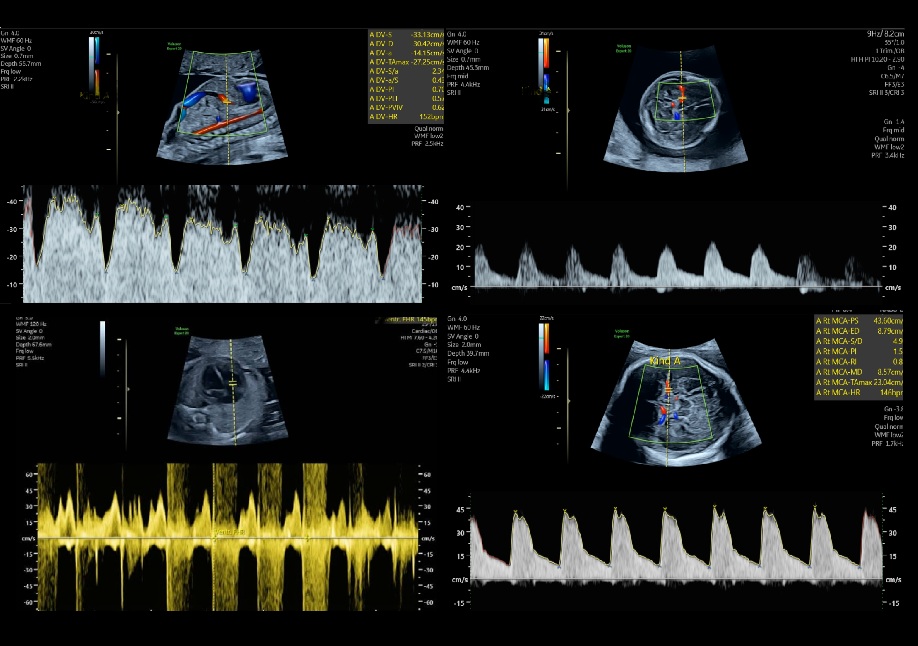

Deze exclusieve training wordt aangeboden in samenwerking met dr. Pascale G. Robles de Medina van Amsterdam UMC, expert op het gebied van o.a. de foetale circulatie en doppler onderzoek en een bijzonder talent om cursisten mee te nemen in de diepere lagen van ons vak. Zij zal tijdens deze training haar kennis en jarenlange ervaring met ons delen. Daarnaast is Gerjanne de With van GE Healthcare aanwezig als applicatiespecialist.